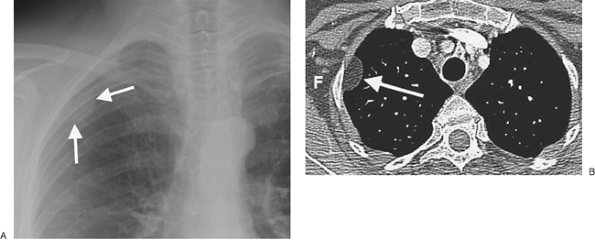

FIGURE 9-28. Pleural lipoma. A: PA chest radiograph coned to the right upper lobe shows a circumscribed mass (arrows) contiguous with the right lateral chest wall. B: CT shows that the mass (arrow) is of homogeneous fat attenuation (F).

FIGURE 9-29. Benign pleural myelolipoma. CT of a 66-year-old woman shows a circumscribed mass abutting the left lateral chest wall. Although the mass contains central fat (arrow), the attenuation of the mass is heterogeneous, and a malignancy, such as liposarcoma, cannot be excluded. The mass was excised and found to be benign.